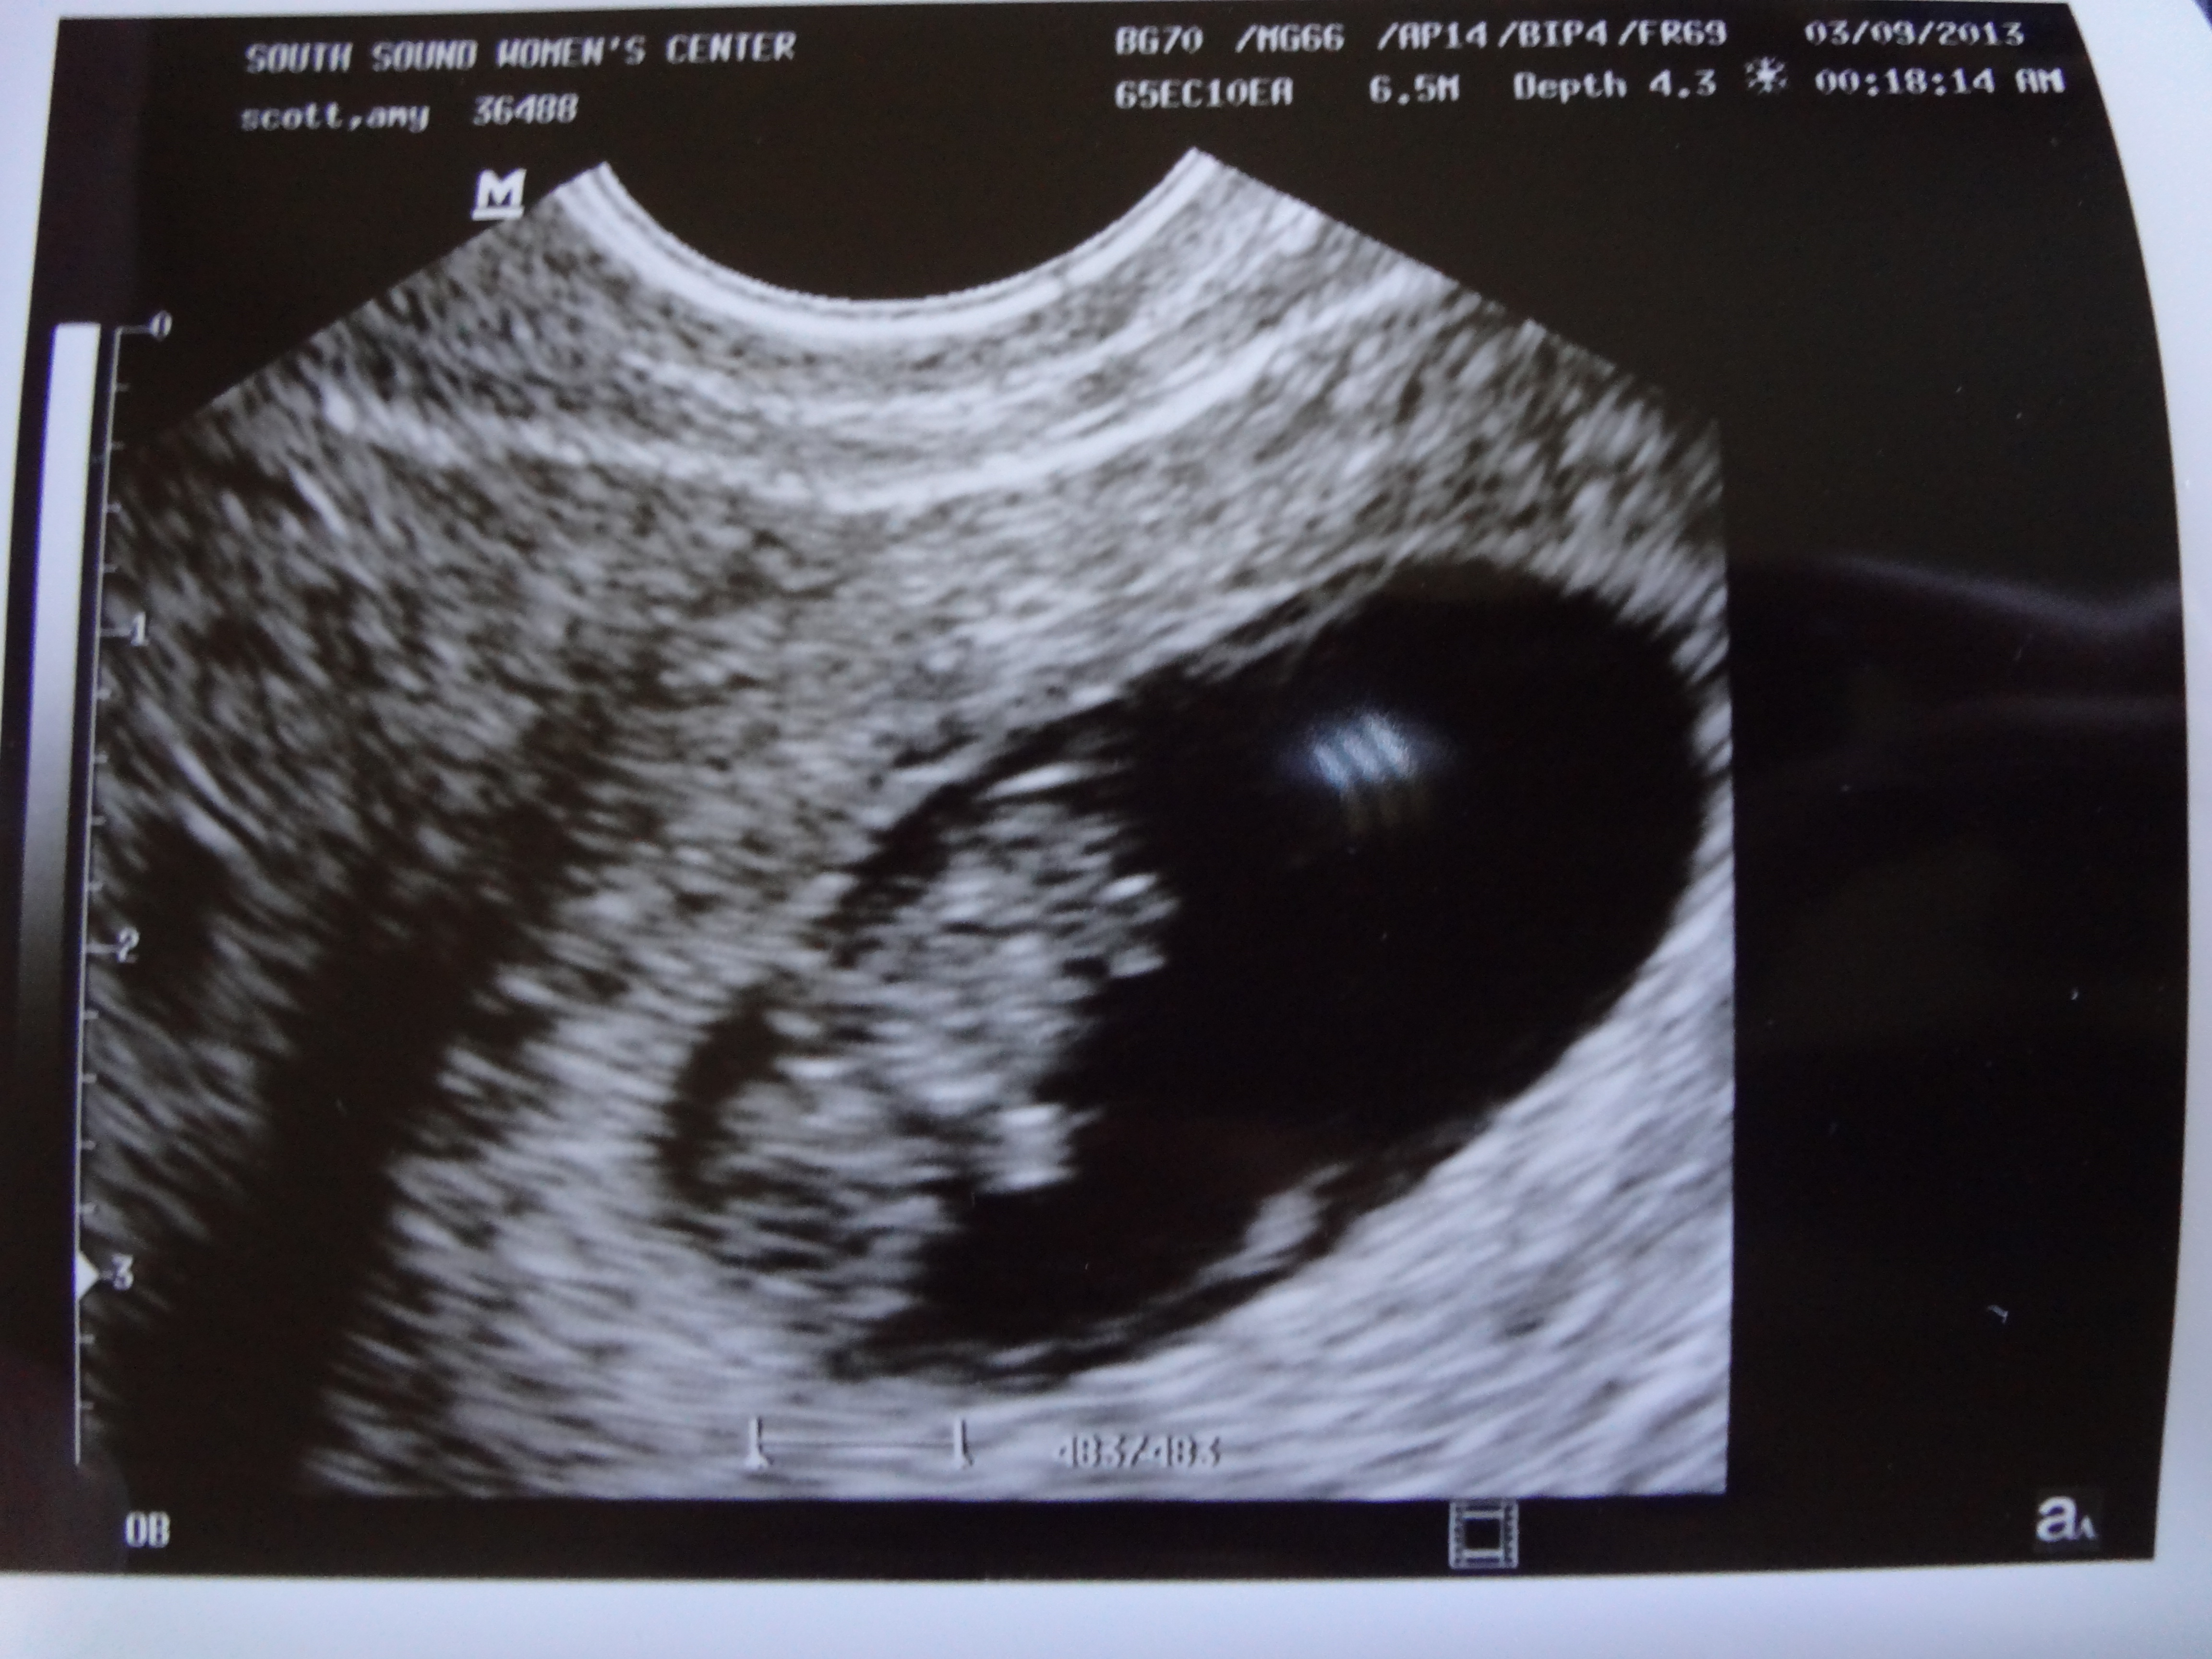

Here are some answers to commonly asked questions. I am 12 weeks along. I have had two doctors appointments and we had an ultrasound. The baby looked healthy and was active. It had a good strong heartbeat. The due date is October 12th and yes, we will find out if we are having a boy or a girl. We might be able to find out as early as our May appointment, but most likely it will be our June appointment. I have less than two weeks left in my 1st trimester and I’m praying that I start to feel better around that time. I’ve been plagued with “morning” sickness that really happens any time of day – mostly morning or evening. I have to pee about 3 times a night and I’m not getting very solid sleep. I guess my body is training me now for what it will be like to get up multiple times a night with the newborn. The combination of sickness and tired has made me wonder why women rave about being pregnant. So far it hasn’t been that great, but I’m hoping things improve soon.